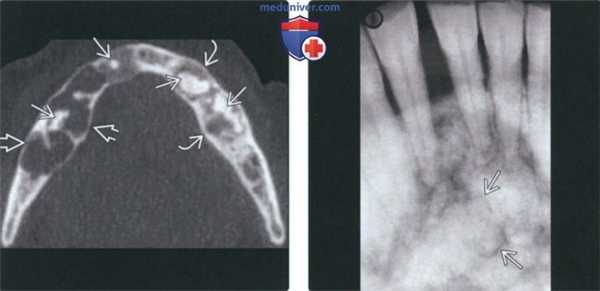

(Слева) На кадрированной панорамной рентгенограмме определяется ФД нижней челюсти справа. Смещение кверху нижнечелюстного канала - патогномоничный признак. Нижний край нижней челюсти вздут, кортикальные пластинки изменены в соответствии с картиной поражения костной ткани. Формирующийся третий моляр смещен кзади.

(Справа) На аксиальной КТ в костном окне определяется картина «матового стекла», характерная для ФД, с вздутием альвеолярного отроака верхней челюсти слева. Щечная и язычная кортикальные пластинки неразличимы. Патологический очаг не пересекает среднюю линию. (Слева) На корональной КЛКТ определяется полиостотическая ФД нижней и верхней челюсти, клиновидной кости, скуловой кости справа. Зернистая картина поражения костной ткани сочетается с «матовым стеклом». Пораженные кости увеличены, но их форма в целом сохранена.

(Справа) На корональной КТ в костном окне определяется ФД, окружающая левую верхнечелюстную пазуху, приводящая к уменьшению ее объема и элевации дна носовой ямки слева. Поражение также распространяется кверху и приводит к смещению кверху дна глазницы. (Слева) На панорамной рентгенограмме определяется ФД в виде «апельсиновой кожуры» между корнями премоляров нижней челюсти слева. Очаг имеет четкие края и смещает корни зубов в стороны.

(Справа) На КЛКТ у этого же пациента определяется истончение и вздутие щечной кортикальной пластинки. Обратите внимание на изменение твердой пластинки и верхней кортикальной пластинки нижнечелюстного канала в соответавии с картиной поражения кости. Канал не смещен и не сдавлен.